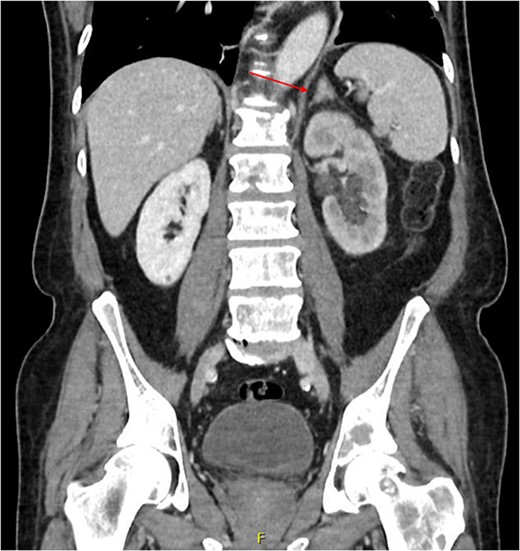

Computed tomography (CT) of the thorax, abdomen and pelvis was requested for staging. Lymphadenopathy was present superior and inferior to the diaphragm, left-sided hydronephrosis with reduced enhancement of the left kidney and widespread mixed lytic and sclerotic lesion affecting the skeleton. The bulky left adrenal gland was concerning for adrenal metastasis (Fig. 3). There was also abnormal urothelial enhancement in the left distal ureter for 4 cm, raising the suspicion of urothelial malignancy (Fig. 4). Blood tests showed a normal prostate specific antigen, mild acute kidney injury, CA19–9 of 17 256 and a carcinoembryonic antigen of 18.

Coronal CT abdomen and pelvis scan with contrast demonstrating left-sided hydronephrosis and left-sided adrenal mass (red arrow).